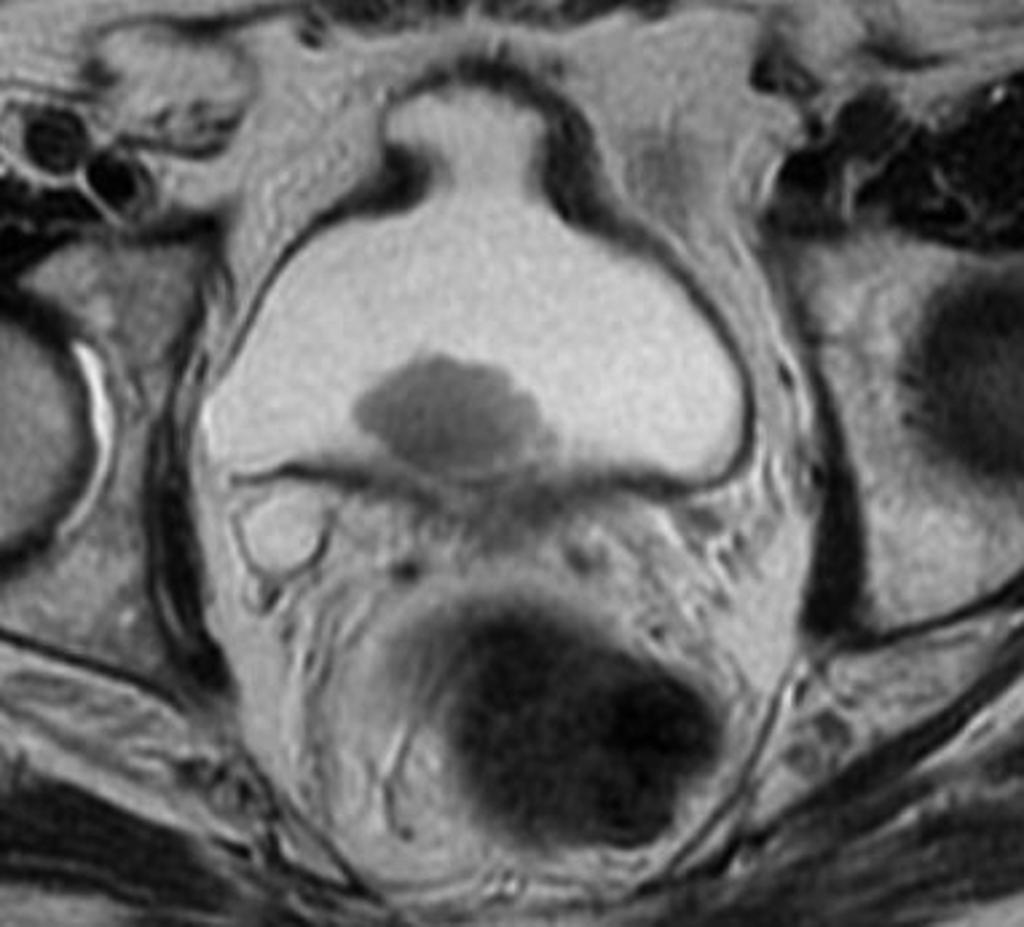

Enhanced MRI showing a bladder tumor at the left wall (arrow). Arrow…

Bladder carcinoma MRI | Urology News

Bladder cancer MRI – wikidoc

mpMRI of a male patient with stage T1 high-grade bladder cancer 3 …